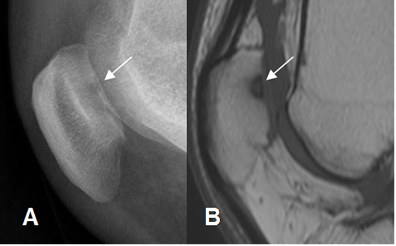

Fig 170. Condromalacia patelar grado 4.

A: Rx lateral y B: RM sagital en T1. Lesión del cartílago articular, con defecto óseo en la patela, por condromalacia G 4.